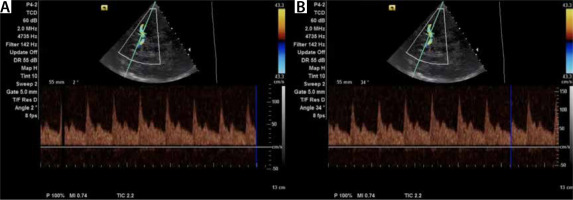

Using TCCD, angle correction can be performed to avoid a potential source of error. Angle correction improves the accuracy of TCCD for the detection of elevated ICP (Figure 4) [20].

TCCD demonstrates sensitivity of 90% and specificity of 71% for the detection of severe vasospasm [4]. Vasospasm following subarachnoid haemorrhage contributes to a 15–20% risk of stroke or death [3]. It is estimated that vasospasm occurs in 30–70% of patients after aneurysm rupture. Typically, vasospasm does not occur until day 3. Its frequency peaks between days 6 and 12 and falls 15–20 days after the haemorrhage [2]. Flow velocity (FV) is inversely proportional to the diameter of a vessel. Therefore, the greater the severity of vasospasm, the higher the blood FV. This can be observed until the critical stenosis is reached and FV decreases. The parameters needed to identify vasospasm are PSV, EDV, MFV, and RI. The normal Doppler waveform pattern of the MCA has a sharp systolic upstroke with a stepwise diastolic deceleration (Figure 5). A normal MFV for the MCA is usually 80 cm s–1 or lower. The MFV cut-off value for the absence of vasospasm in the MCA is below 120 cm s–1. Values between 120 and 200 cm s–1 indicate mild to moderate vasospasm. MFV higher than 200 cm s–1 is indicative of severe vasospasm. Increased values of MFV are insufficient to diagnose vasospasm. The diagnosis should include clinical assessment, as hyperaemia, hypertension, or hypervolemia may be responsible for vasospasm [2–5, 7, 13, 15, 19, 21–23, 25–31].

FIGURE 5

Normal Doppler waveform pattern of the middle cerebral artery with a sharp systolic upstroke followed by a stepwise diastolic deceleration